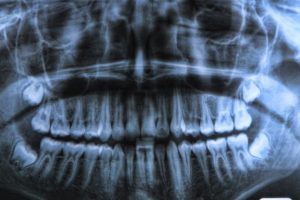

دندان عقل

دندان عقل از آن دسته اندامهاست که تحلیلرفته (Vestigial) میخوانیمشان. اندام تحلیل رفته به اعضایی گفته میشود که یادگار دورانهای گذشته هستند. این اندامها زمانی کاربردی معین داشتهاند، اما امروز فقط فضایی از بدن را اشغال کردهاند. به عبارتی این اندامها نه نشان از انطباق، که از عدم انطباق خبر میدهند. در این مورد، عدم تطبیق دندانها، خاطرات ناخوشایندی از عصبکشی را برای خیلی از ماها به دنبال داشته است.

بشر در گذشته جمجمههای پهنتری داشته و همین مستلزم دندانهای بیشتری بوده است. دندانهای عقل در آن زمان کاربردهای موثری در جویدن و شکستن غلاف انواع غذاها داشتهاند. به مرور که انسان پیشرفت کرد و با خوراکهای لذیذی مثل ماست چکیده آشنا شد، دندانهای آسیای انتهایی ما مشمول تعدیل نیرو شده و کنجنشین شدند. علت نامگذاری این دندانها این است که عموما در دهه سوم زندگی میرویند. شاید نامگذاری این دندانها آخرین رکب ریشسفیدها برای ترغیب جوانترها به ازدواج بوده باشد! در هر حال با حقایقی که امروزه میدانیم، شایستهتر است که این دندانها را دندانهای خرفت بخوانیم!